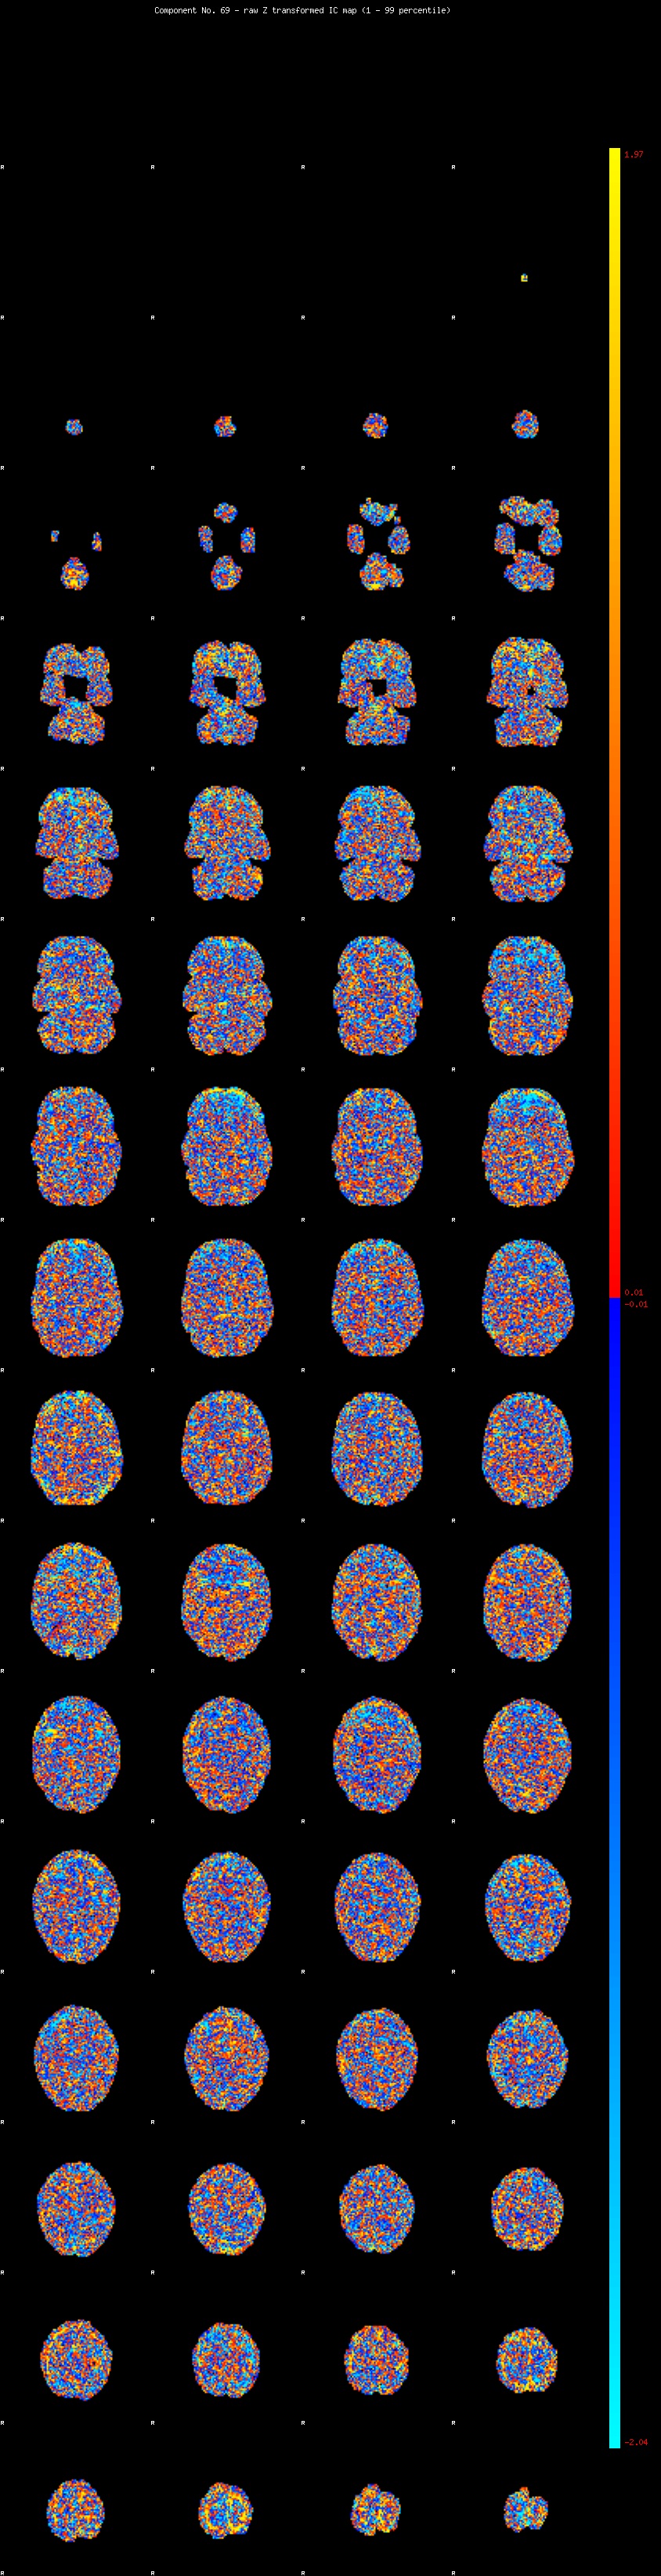

IC_69 Mixture Model fit

Means : -0.000000 2.035350 -2.051938

Vars : 1.000000 0.712266 0.735757

Prop. : 0.910897 0.038995 0.050108